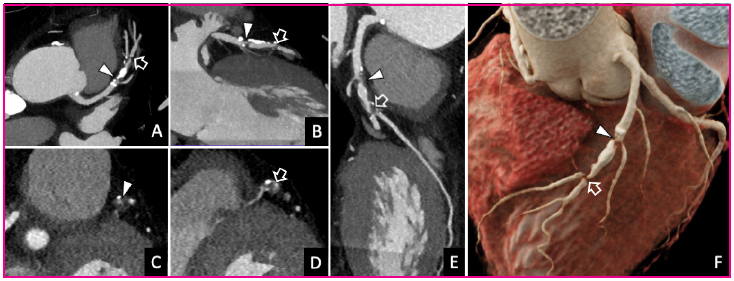

Fig. 1 Coronary CT angiography. A, B: Multiplanar reconstructions of the left anterior descending coronary artery. C, D: Reconstructions perpendicular to the long axis of the vessel. E. Curved planar reconstruction. F. Kinematic volumetric reconstruction. The study demonstrated 70-99% stenosis in the mid third of the left anterior descending coronary artery, which involves its origin (arrowhead) and second diagonal branch (hollow arrow).

A coronary computed tomography angiography (CCTA) was requested to study the symptoms reported by the patient (Figure 1). The right and circumflex coronary arteries were diffusely ill, with calcified and non-calcified plaques that caused < 50% stenosis. A large calcified and non-calcified plaque of about 23 mm length was observed located in the mid left anterior descending coronary artery, at the ostium of the diagonal branches, that caused lumen stenosis of 70-99%. Given these findings, it was decided to complete the exploration using stress CT-perfusion with a vasodilator drug (regadenoson) (Figure 2). The test was positive for myocardial ischemia in the territory corresponding to the left anterior descending coronary artery. The study was classified as CAD-RADS 4A/P3/I+ (corresponding to severe stenosis with a large size plaque and demonstration of ischemia). With this result, the patient was referred to the Hemodynamics service, where a catheterization, that confirmed the serious lesions described in the CCTA (Figure 2), was performed. The first stenosis was treated with stent implantation. The most distal lesion could not be treated percutaneously because the vessel was sub-occluded. Finally, it was treated by aortocoronary bypass surgery with a graft from the left internal mammary artery to the mid left anterior descending coronary artery and from the saphenous vein to the diagonal branch.